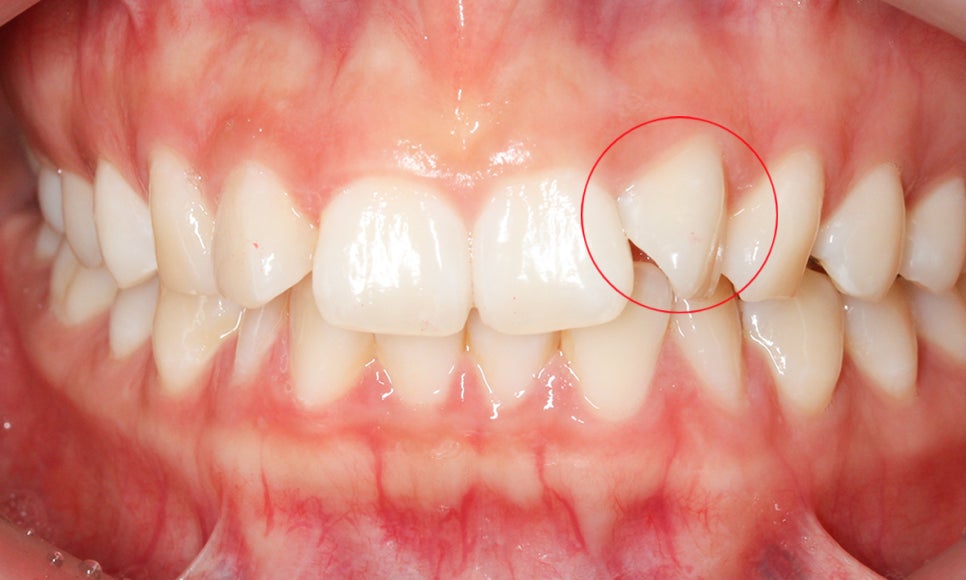

아래의 Case는 세라믹교정 을 진행한

앞니틀어짐 사례로 보시는 것처럼

상악 측절치의 각도가 틀어져 있어

교정이 필요한 모습인데요,

교정 전 정밀진단 1차

세라믹교정 전 정밀진단을 통해

치아의 상태를 확인한 결과

상악 측절치의 각도가 약 90도 가량

틀어져 있는 것을 확인하였습니다.

정면에서는 보이는 것 처럼

치아의 앞면이 아닌 측면이 보이는 모습으로

이러한 앞니틀어짐 증상을 흔히 덧니라고

오인하고 내원하시는 분들이 많은데요

덧니와 앞니틀어짐을 구분하는 방법은

잇몸라인과 치아가 맹출된 높이를

확인하시면 쉽게 파악하실 수 있습니다.

위의 앞니 틀어짐 case의 경우

상악 측절치가 맹출된 높이를 보시면

치아의 각도를 제외하고 주변 치열과

크게 이질적인 느낌은 들지 않는데요,

잇몸 라인도 일정하게 구치부까지

이어지는 모습으로 해당 치아는

덧니라고 보기에는 어려움이 있습니다.